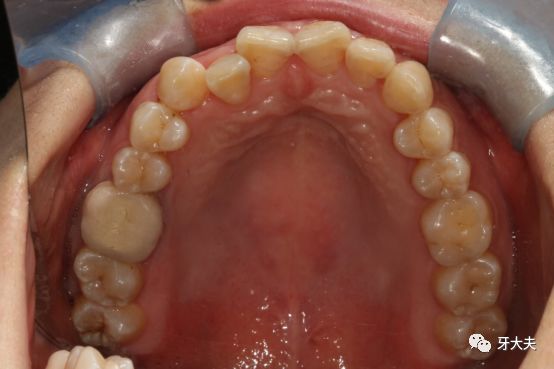

2月27日,等待了两个月,终于等来了我的牙套,带上去不近看的话,真的看不出我带了牙套! 刚刚戴上的那一刻,真的像医生所说的那样,像绷紧的鞋带一样,戴了一会后,开始感觉牙套在加力,牙齿微微有些酸痛,过了一天后,基本没有感觉。 过了12天,开始戴第二幅牙套啦,牙齿有些细微的变化 第三副牙套了,粘了附件,附件感觉有点明显。 医生和我说,这些白色小附件主要是辅助牙齿移动和增强固位的。在佩戴隐形牙套的期间,附件需要与矫治器紧密贴合才能发挥辅助牙齿移动,增强固位的作用。虽然丑,也只能这样接受了(摊手) 目前,已经戴牙套带到了第五副,时间过的好快,1个多月已经过去了。从最开始戴牙套时的有点大舌头,到现在完全不影响,它已经慢慢融入了我的生活。附上近照一张。期待它慢慢的改变~ 小经验分享